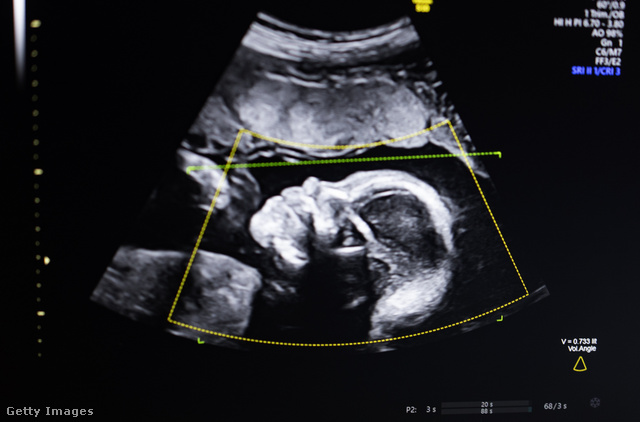

Ami az emberi szervezetet illeti, a korábbi kutatások során a vérben, tüdőben, székletben, illetve méhlepényben is bukkantak már mikroműanyagokra. Az utóbbi lelőhely lehet igazán aggasztó: a kutatók egyre több placentát vizsgáltak meg, és egészen sokkoló eredményre jutottak.

2021-ben jött az első bejelentés egy kutatócsoporttól, amely négy méhlepényben detektálta mikroműanyag keringését. Nemcsak a lepény anyához közelebb eső területén, de a magzathoz közel található rétegében, sőt, még magában a magzatburokban is bukkantak ekkor apró műanyagdarabkákra. 2023 elején egy újabb kutatás 17 placentában mutatta ki az anyagot, tavaly év végén pedig hawaii kutatók dolgoztak 30 méhlepénnyel, melyeket 2006-tól kezdve adományoztak a szülő nők tudományos célokra. Nem fog meglepni, hogy ezek mindegyikében is ott voltak az apró műanyagdarabok.

Az anya vagy a magzat egészségére gyakorolt konkrét hatást egyelőre nem tudtak kimutatni a placentában található műanyagok esetében, az ugyanakkor tény, hogy a méhlepény egy nagyon fontos, érzékeny szerv, mely a magzatok fejlődésében kulcsszerepet játszik. Ez a komplex szövet gondoskodik a magzatról anyaméhbeli fejlődése során, feladata a kórokozók és más potenciálisan veszélyes anyagok kiszűrése az anya véráramából, miközben különböző tápanyagokat, antitesteket és oxigént juttat számára.

Jóval több, mint védőfal: a hormonok és a gondosan időzített biokémiai reakciók finom egyensúlya által irányított, változatos és dinamikus sejtrendszerekből áll. Ebbe az evolúció során évmilliók alatt kialakított rendszerbe avatkoznak be most a mikroműanyagok, ki tudja, pontosan milyen hatást okozva.